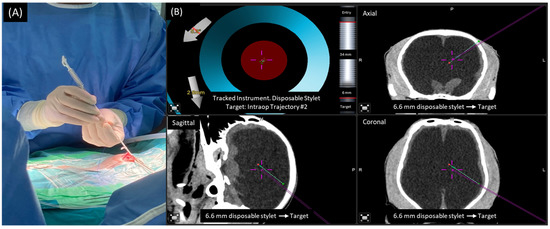

2.1. Treatment